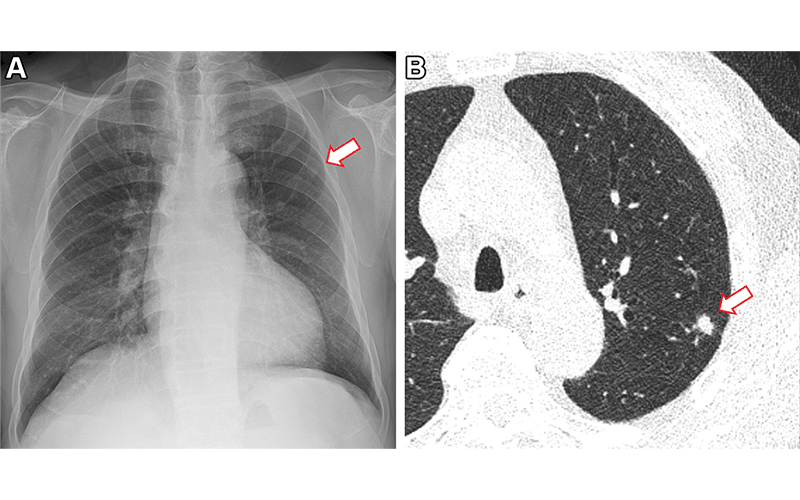

Images in a 73-year-old man who underwent chest radiography and low-dose CT for health checkup purposes and was allocated to the non–artificial intelligence (AI) group. (A) Frontal chest radiograph shows a small nodular opacity (arrow) in the left upper lung zone, which was missed by the designated reporting radiologist. (B) Axial, noncontrast, low-dose chest CT scan shows a 9-mm solid nodule (arrow) in the left upper lobe. The nodule showed low metabolism at PET and decreased in size at follow-up CT. It was confirmed to be an inflammatory nodule.